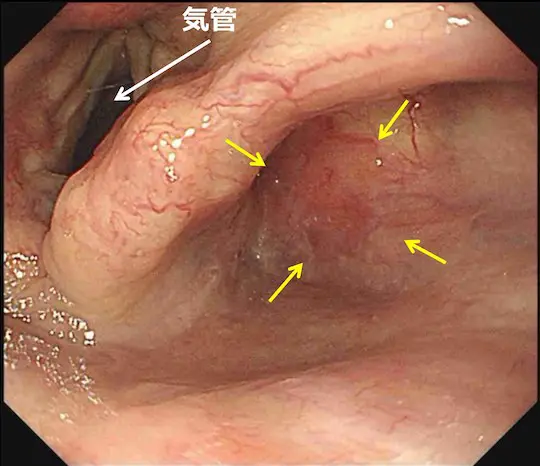

黄色い矢印で示す部分が少し赤くなっています。この部分が咽頭癌です。非常に分かりにくい病変です。

ヨードと呼ばれる薬液で染色すると、白い矢印で示す部分に咽頭癌(周りと色の違う部分)が浮かび上がってきます。